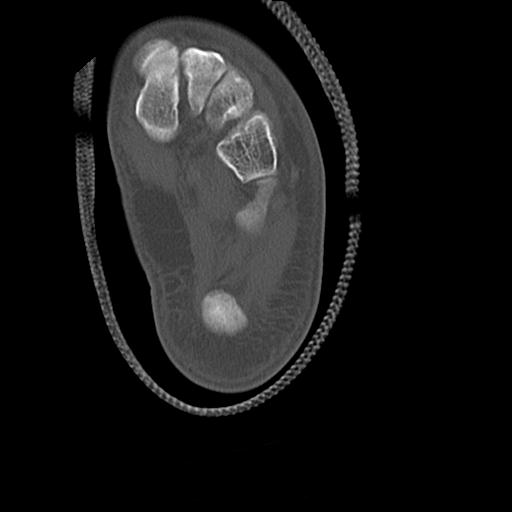

56476 8/28 4R 1/21 2R 左足関節 デジカメ写真 72歳女性 右足関節AS